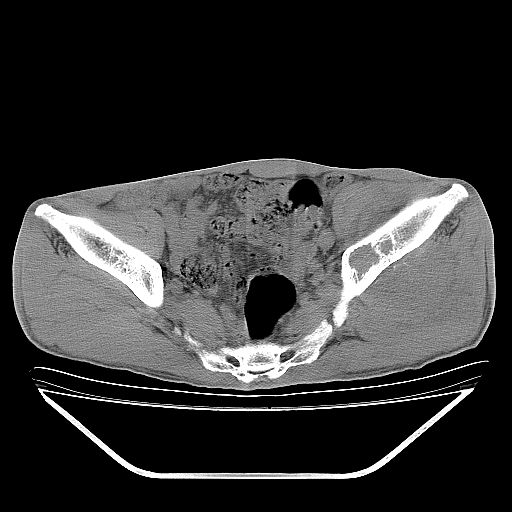

以下是引用天南地北在2007-10-4 18:01:00的发言:[br][br]考虑左髂部恶性肿瘤(溶骨性骨质破坏+软组织肿块影+残留骨质);以滑膜肉瘤可能性大。[br]建议穿刺活检

以下是引用liuyue在2007-10-4 23:38:00的发言:[br]左髂部恶性肿瘤,建议穿刺活检,或先做肺部检查,除外肺癌转移之可能。